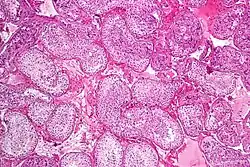

Seminiferous tubule with maturing sperm. H&E stain. | |

Spermatogenesis is the process by which haploid spermatozoa develop from germ cells in the seminiferous tubules of the testicle. This process starts with the mitotic division of the stem cells located close to the basement membrane of the tubules.[1] These cells are called spermatogonial stem cells. The mitotic division of these produces two types of cells. Type A cells replenish the stem cells, and type B cells differentiate into primary spermatocytes. The primary spermatocyte divides meiotically (Meiosis I) into two secondary spermatocytes; each secondary spermatocyte divides into two equal haploid spermatids by Meiosis II. The spermatids are transformed into spermatozoa (sperm) by the process of spermiogenesis. These develop into mature spermatozoa, also known as sperm cells.[2] Thus, the primary spermatocyte gives rise to two cells, the secondary spermatocytes, and the two secondary spermatocytes by their subdivision produce four spermatozoa and four haploid cells.[3]

Spermatogenesis starts in the bottom part of seminiferous tubes and, progressively, cells go deeper into tubes and moving along it until mature spermatozoa reaches the lumen, where mature spermatozoa are deposited. The division happens asynchronically; if the tube is cut transversally one could observe different maturation states. A group of cells with different maturation states that are being generated at the same time is called a spermatogenic wave.[5]

Spermatogenesis takes place within several structures of the male reproductive system. The initial stages occur within the testes and progress to the epididymis where the developing gametes mature and are stored until ejaculation. The seminiferous tubules of the testes are the starting point for the process, where spermatogonial stem cells adjacent to the inner tubule wall divide in a centripetal direction—beginning at the walls and proceeding into the innermost part, or lumen—to produce immature sperm.[2] Maturation occurs in the epididymis. The location [Testes/Scrotum] is important as the process of spermatogenesis requires a lower temperature to produce viable sperm, specifically 1°-8 °C lower than normal body temperature of 37 °C (98.6 °F).[6] Clinically, small fluctuations in temperature, such as from an athletic support strap, cause no impairment in sperm viability or count.[7]